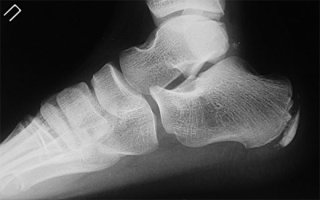

Остеофит можно спутать с многократно повторяющимися сухими мозолями на пятке. На ощупь отличия между костным, сухожильным наростом не всегда ощутимы, поэтому некоторые пациенты не торопятся к врачу за диагнозом. Помимо визуального осмотра стоп на предмет вальгусной/варусной деформации пациенту назначают рентгенографию, которая покажет, в чем причина шишки на пальце: остеофит или воспаление сухожилий – ретрокальканеальный бурсит. От диагноза зависит план лечения.

Если рентген не показал признаков костного нароста на пятке, больному назначается магнитно-резонансная томография стоп для уточнения диагноза, установления степени воспаления сухожилий, причин. Шишка на пятке сбоку – основание полагать, что у пациента не остеофит, а воспаление мягких тканей. Избавляться от натертостей на пяточках можно в домашних условиях с помощью отваров из лечебных трав, заменой обуви на комфортную.